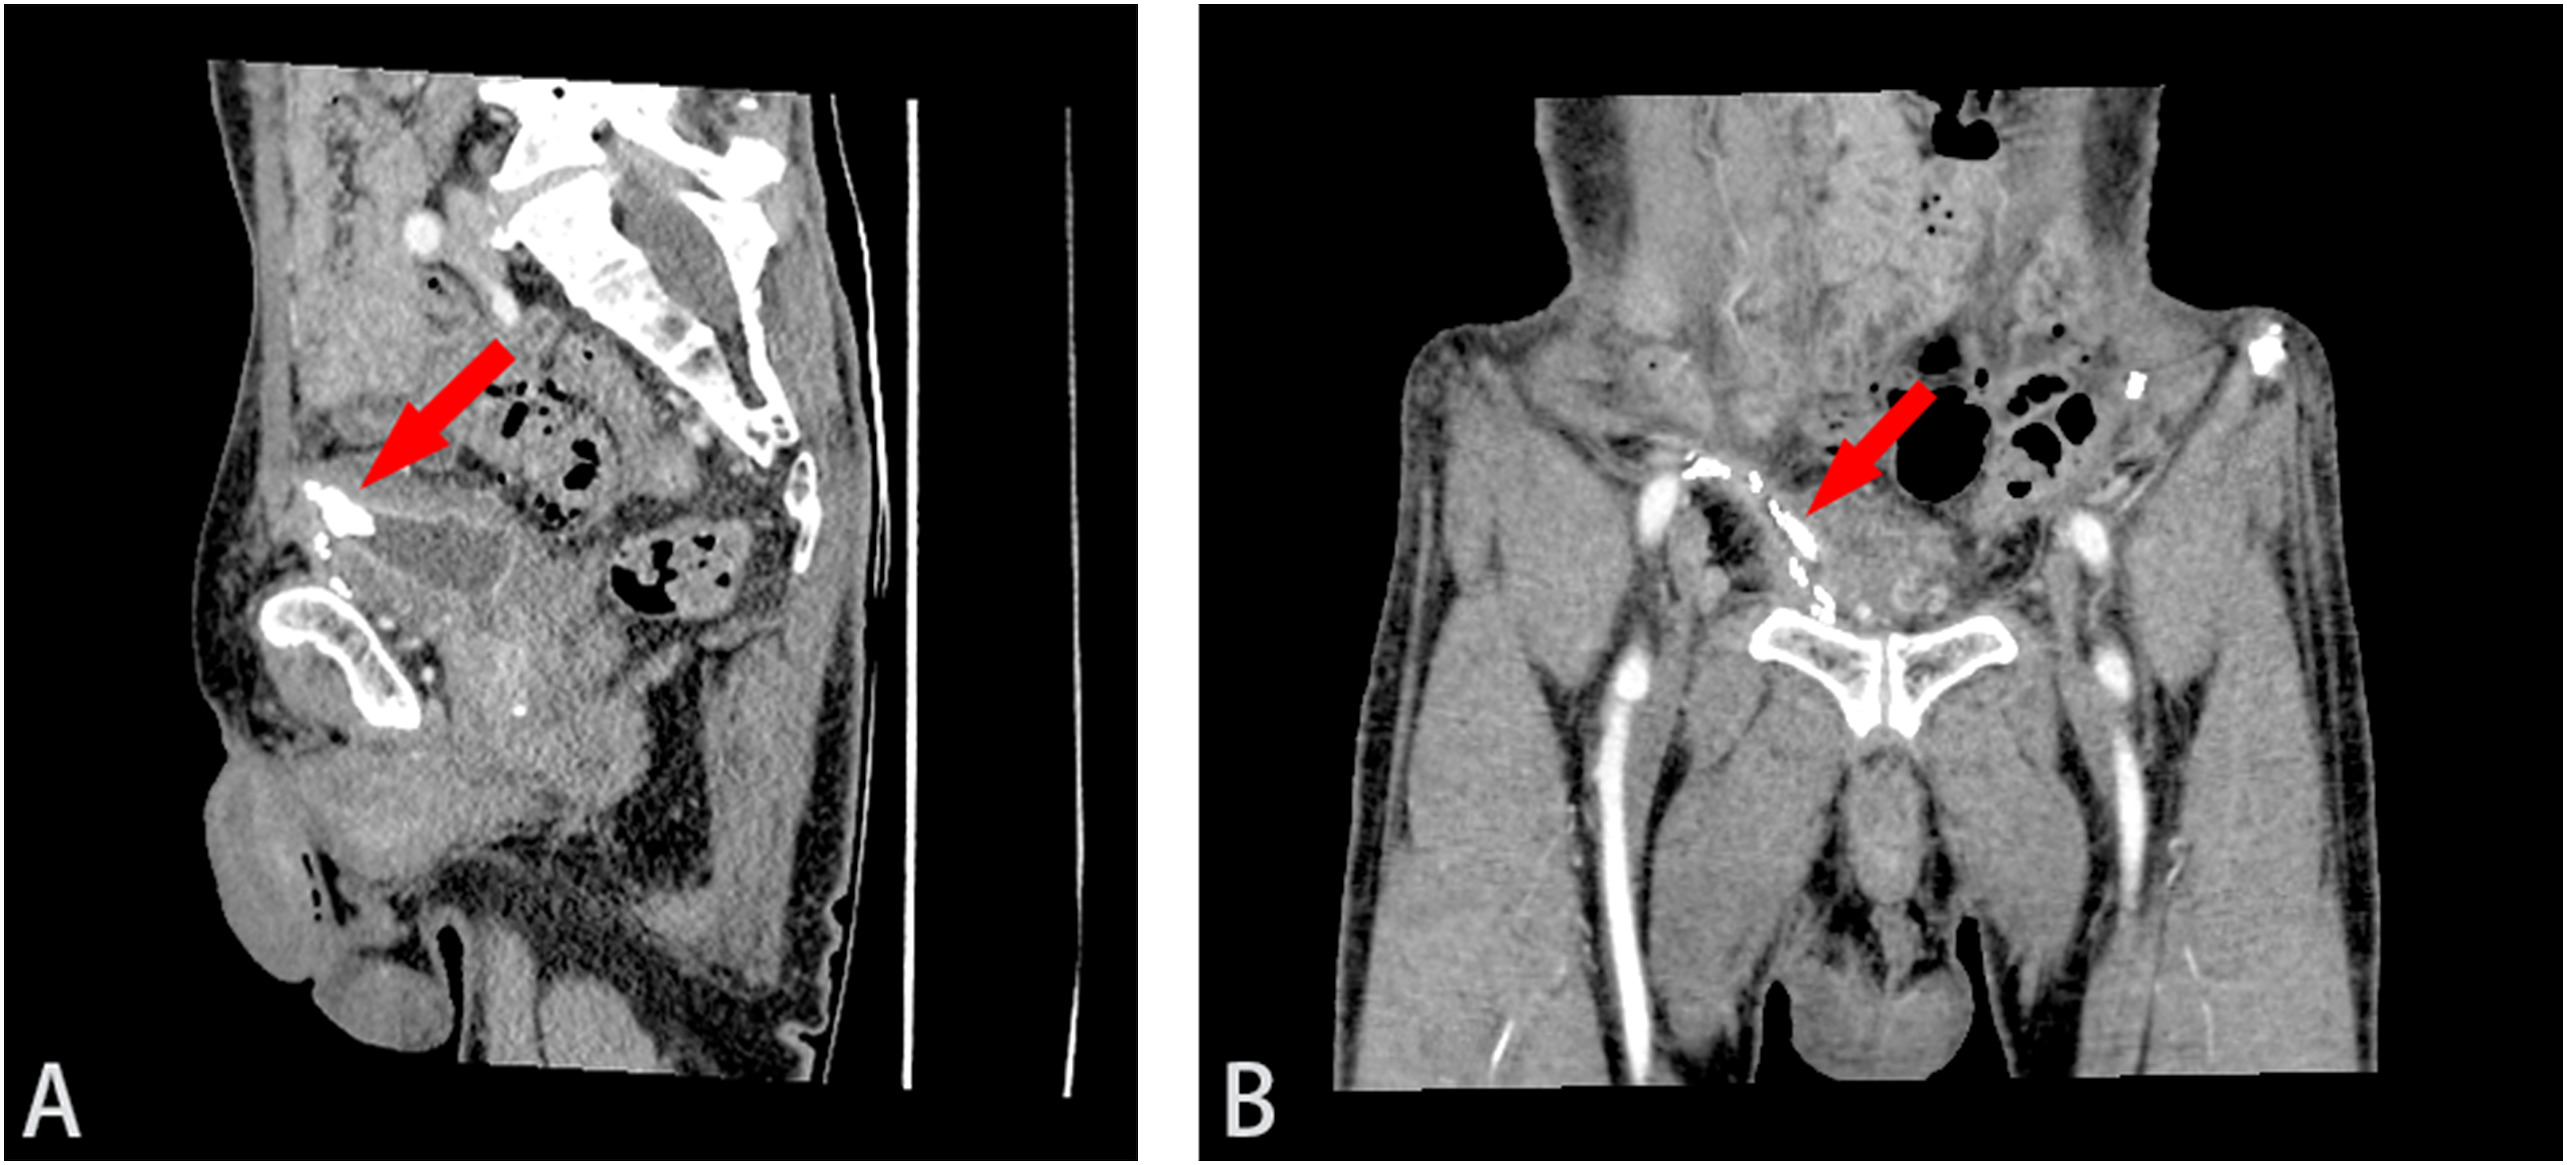

图2 (A)CT矢状位和(B)冠状位。3D-CT重建显示补片侵蚀膀胱,结石与网片紧密粘连(红色箭头)

显示,膀胱前壁上附着一大小约17×14×10mm的结石,骨盆内有多个金属钉,怀疑是用于固定补片的手术钉(图1B)。三维重建CT(3D-CT重建)显示补片侵蚀膀胱,结石与网片粘连紧密(图2)。膀胱镜

可显示膀胱结石或网片上的钙化沉积物。CT(尤其是3D-CT重建)可以清晰地显示膀胱、结石和网片的空间关系。CT尿路造影和膀胱镜检查对最终的诊断很重要。膀胱镜检查可以直接观察膀胱结石或网片对膀胱的侵蚀。有时由于结石覆盖,可能无法直接显示网片。